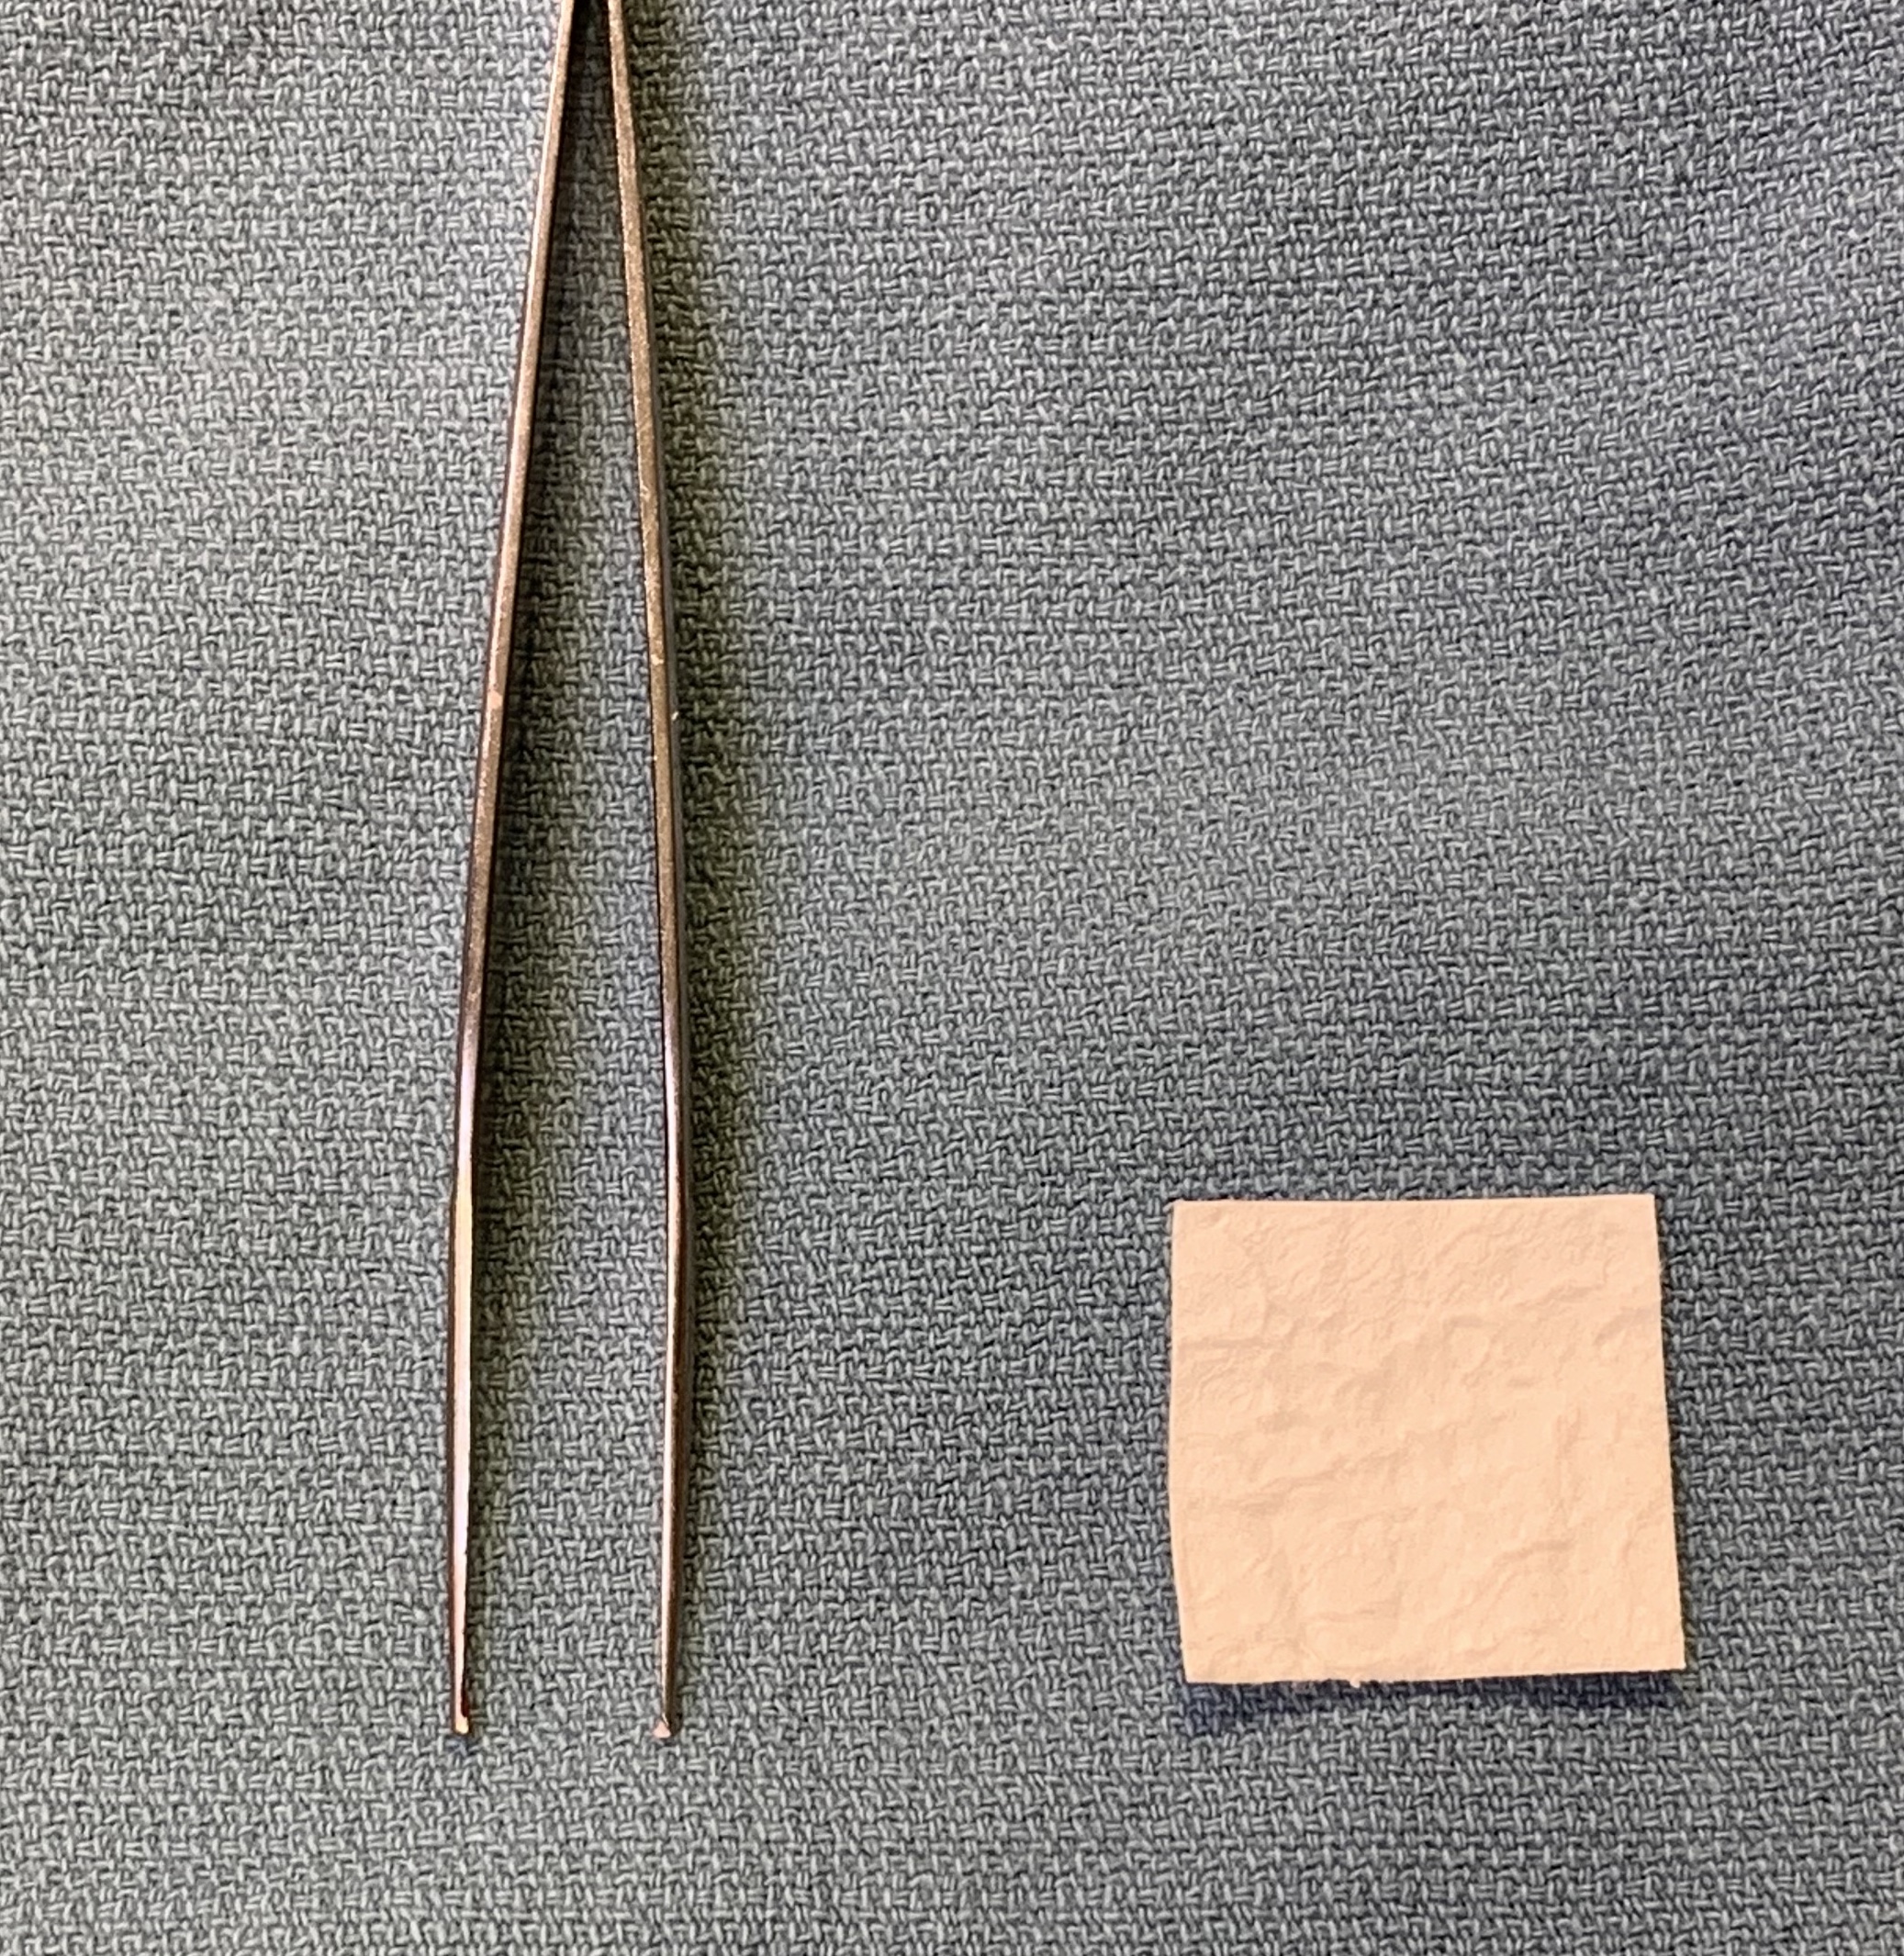

Metatarsal bar / premetatarsal dome to unload MT head